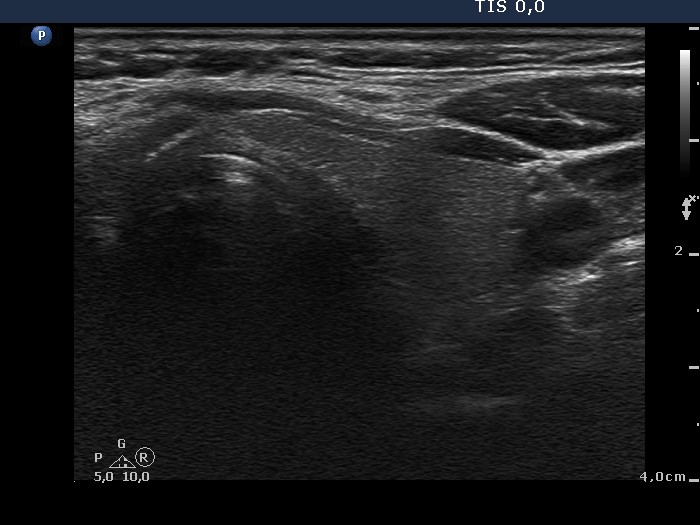

Benign nodular hyperplasia - Case 59. (ultrasonographic picture 7)

Left lobe, horizontal view. This lobe is intact.